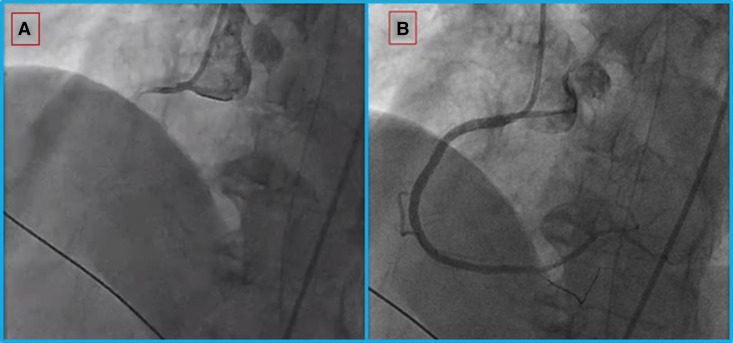

Emergent cardiac catheterization revealed multivessel coronary disease, including a completely occluded right coronary artery, which was revascularized with drug-eluting stents leading to restoration of Thrombolysis in Myocardial Infarction (TIMI) 2 to 3 flow (Figure 1).

Figure 1.

Coronary angiography for the woman in Case 1. (A) Proximal total occlusion of the right coronary artery; (B) after extensive angioplasty and stent implantation, flow is restored.